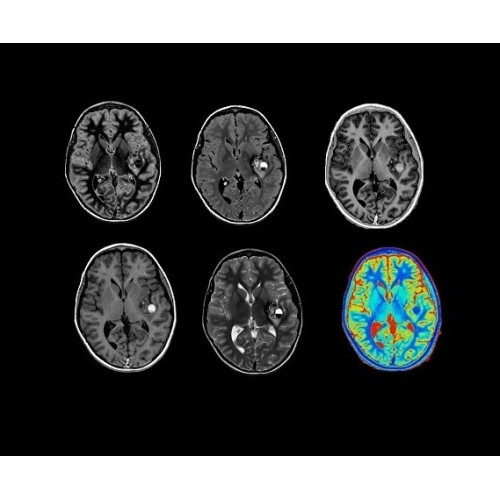

SIGNA Architect 3.0T — это новейший МРТ аппарат компании GE, который предлагает высочайший уровень производительности — в системе 128 приемных каналов, 48 канальная катушка головы, полный спектр клинических возможностей. Высокий уровень комфорта пациента обеспечивают такие особенности как отсоединяемый стол, положение пациента «ногами вперед» для всех видов исследований, SilentWorks — бесшумное и MAGIC — быстрое сканирование.

Теперь возможности МРТ поражают еще больше благодаря ультрасовременным решениям для визуализации с SIGNA Architect 3.0 Тл, объединяющей новейшие достижения в области МР-технологий и интуитивно понятный интерфейс. Система SIGNA Architect, разработанная на базе новой платформы SIGNA Works, представляет собой гармоничное сочетание дизайна и функциональности. Каждый элемент системы направлен на повышение производительности, эффективности клинической практики, финансовых показателей, а также комфорта и безопасности пациента.

• NeuroWorks — универсальное решение для визуализации анатомии головного мозга, позвоночника, сосудов и периферических нервов с четкой дифференциацией тканей.

• 48-канальная катушка TDI для головы, входящая в базовую комплектацию SIGNA Architect, обеспечивает феноменальную производительность с учетом особенностей каждого пациента. Благодаря гибкому и универсальному дизайну, высокому соотношению сигнал/шум и передовым технологиям визуализации, таким как HyperWorks, учитываются потребности подавляющего большинства пациентов.